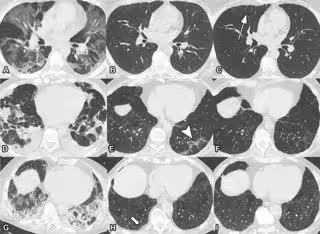

TC torácicos axiales seriados sin contraste de tres participantes en el estudio con neumonía COVID-19 previa.

TC torácicos axiales seriados sin contraste de tres participantes en el estudio con neumonía COVID-19 previa. - RADIOLOGICAL SOCIETY OF NORTH AMERICA